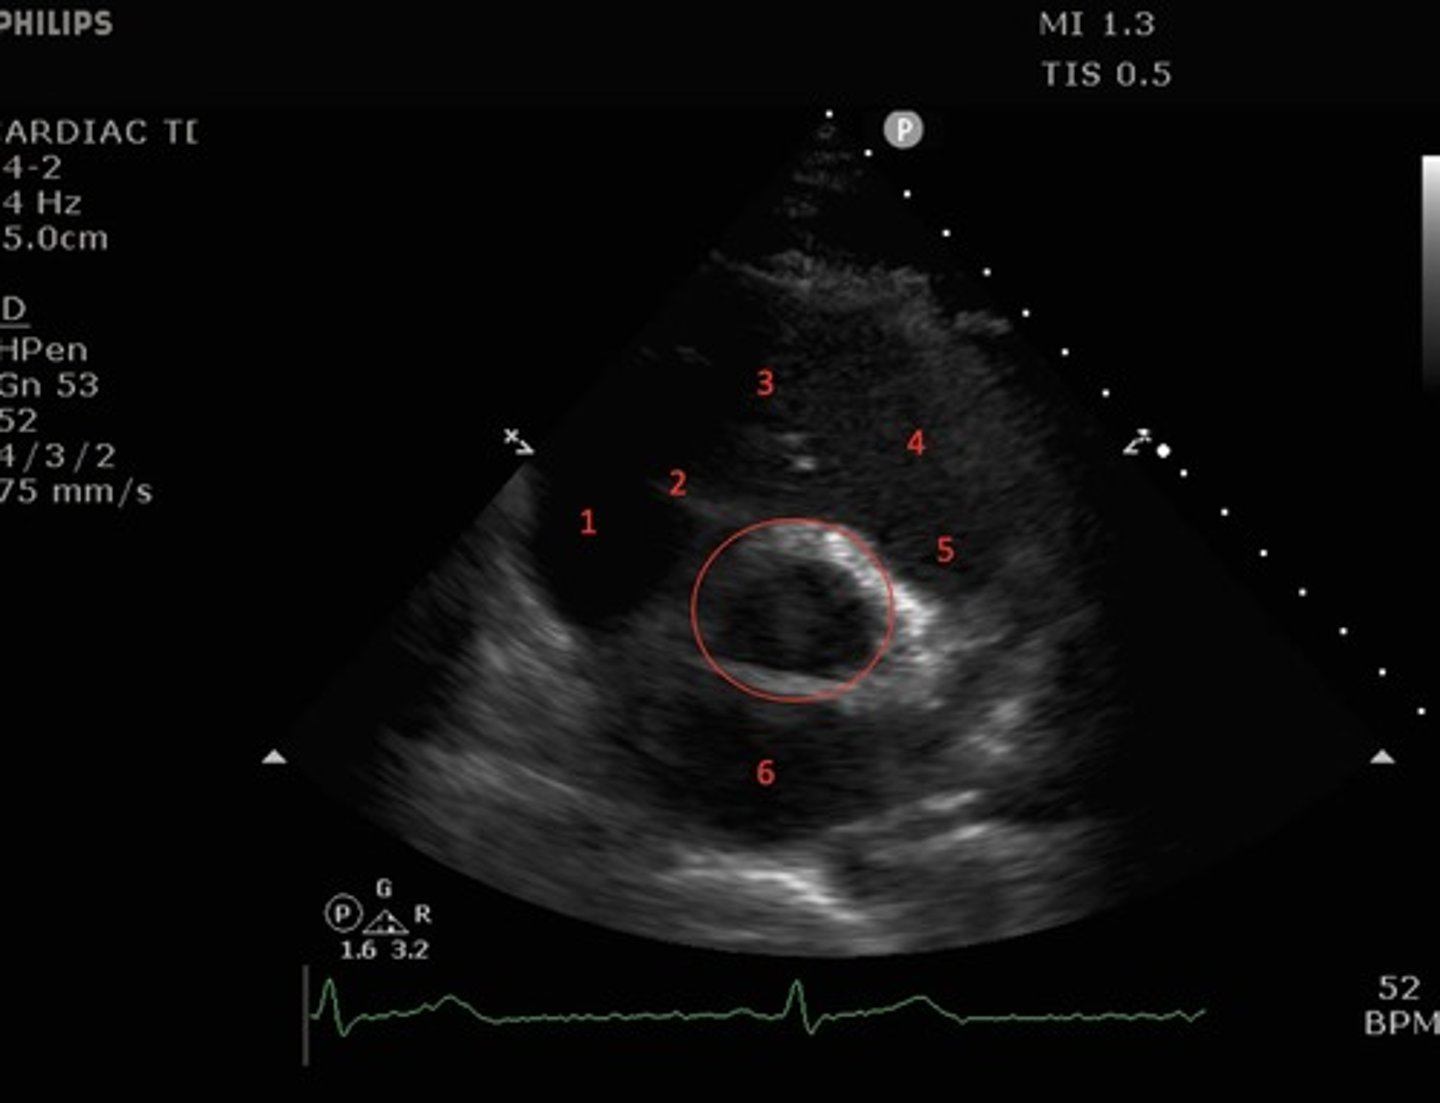

Parasternal short axis mid-ventricle

What view of the heart is this?

right ventricle, left ventricle, papillary muscles of the left ventricle

What structures are shown by the parasternal short axis mid ventricular view?

Papillary muscles

What structures are indicated by the red circles?